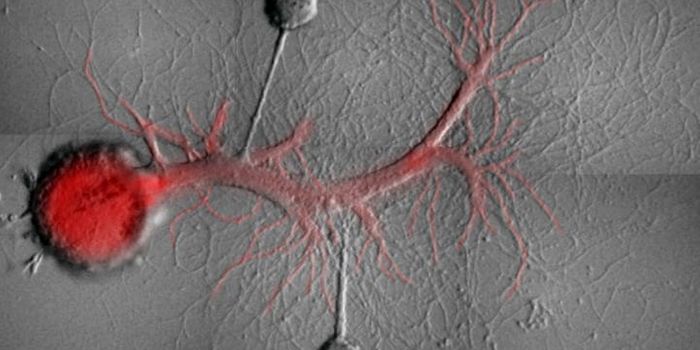

Read the latest articles about newly released neuroscience research and advances in experimental techniques. Topics include research news in neuroscience, neurology, psychology, brain science and cognitive sciences.